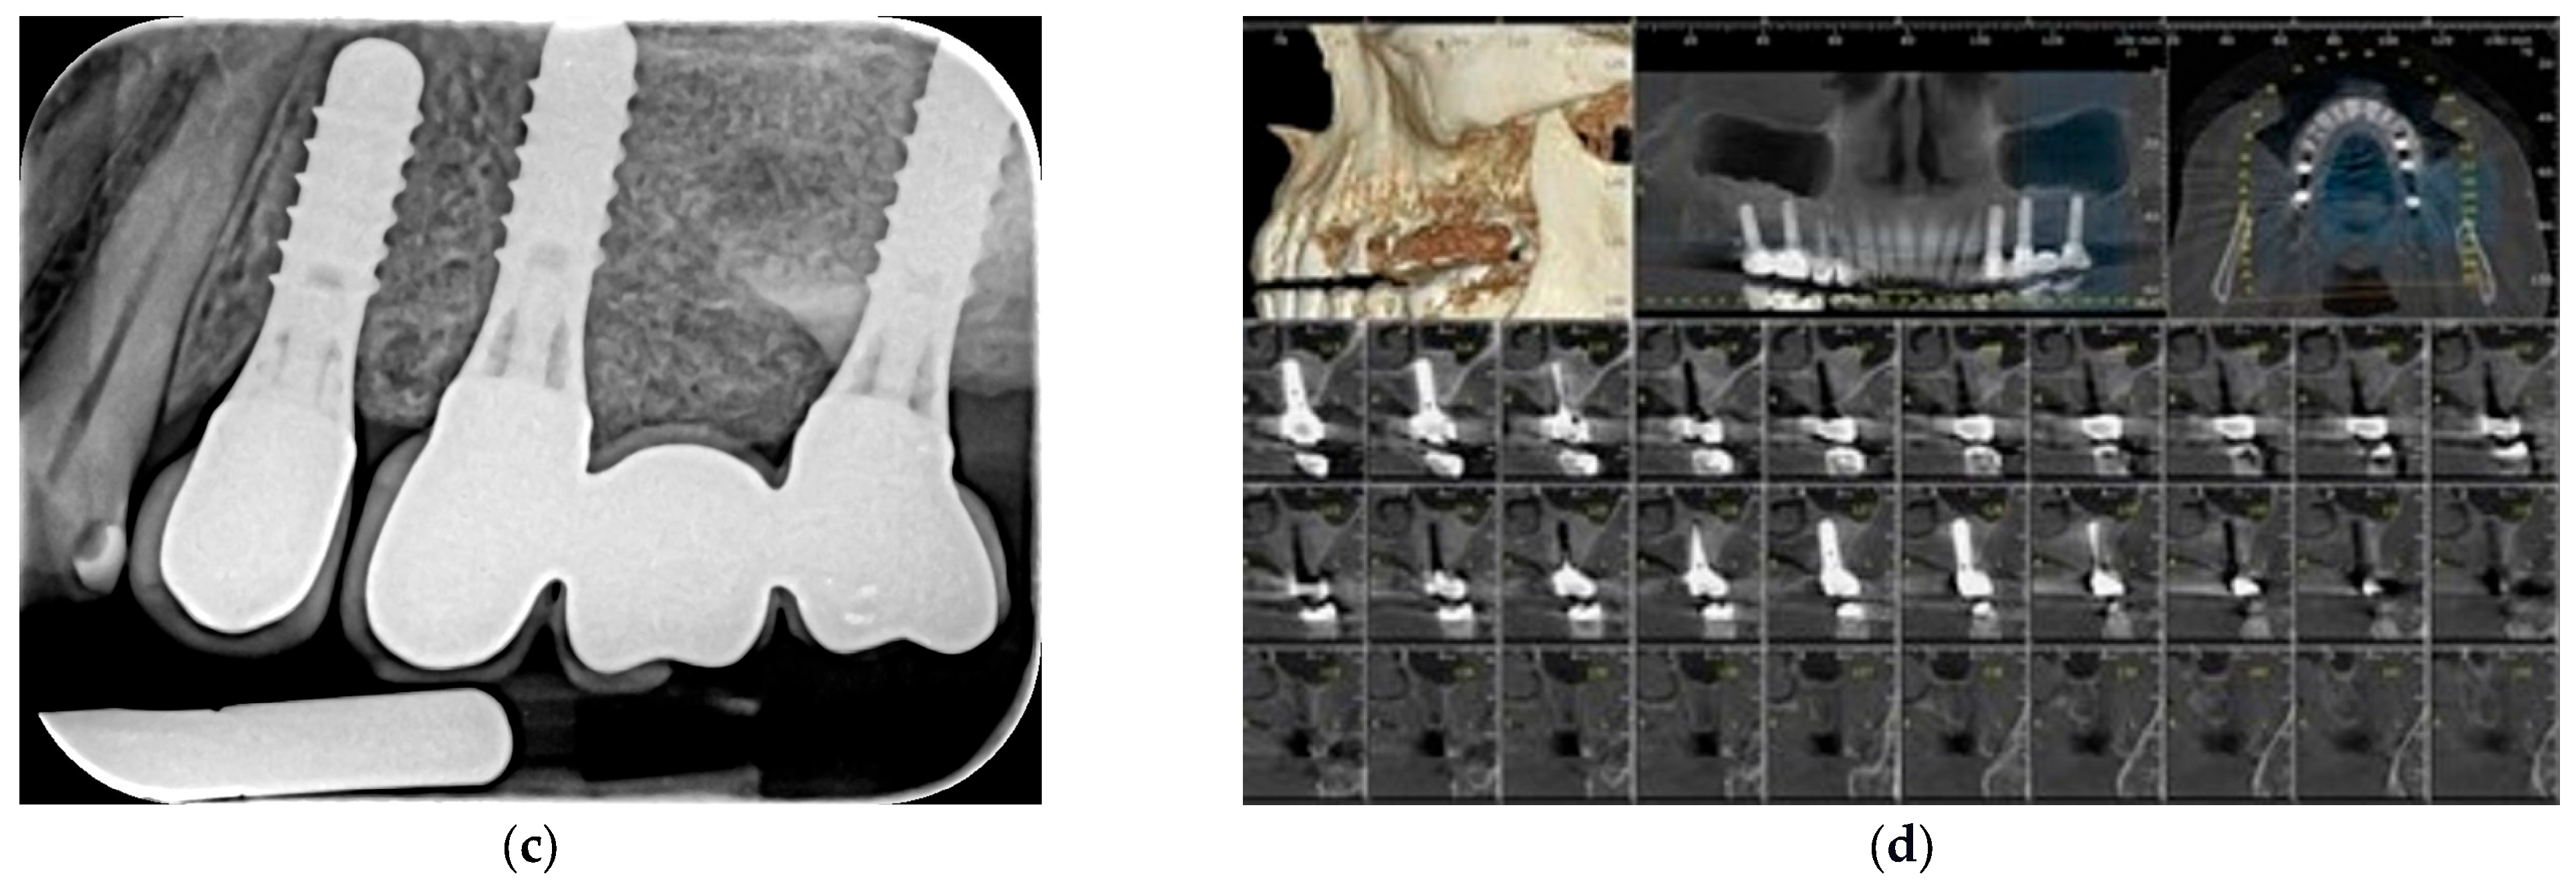

| 1. | F | 49 | 24 May 2021 | Lateral sinus lift with staged implantation | none | none | 4.7 | 2.5.; 2.6.; 2.7. | 2 | 15 | 13 | 52.23 |

| 3. | M | 46 | 22 July 2021 | Lateral sinus lift with staged implantation | none | 7.5 | 2.6.; 2.7. | 1 | 15 | 14 | 38.3 | |

| Months 3–8 | Implant placement and biopsy | Core specimens collected during implant osteotomy; histology (H&E, Masson–Goldner) + TRAP staining |

| Months 12–52 | Follow-up period | Stable marginal bone levels (<1 mm first year); no complications; graft volume maintained |

| 46.8 months (mean) | Long-term evaluation | All implants functional; radiographic and clinical stability confirmed |

| 52.2 months (max) | Long-term | CBCT and periapical radiographs from available case demonstrating stable bone height and osseointegration |